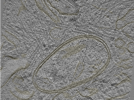

Photo Caption: Central slab from a representative tomogram of a Homo sapiens sample with selected set of annotations.

Cryo-electron tomography of FIB-milled HeLa PINK1-GFP cells treated with 10 uM Gamitrinib-triphenylphosphonium (G-TPP) for 4 hours to induce mitochondrial proteostatic stress. Data includes raw tilt series movie frames, assembled tilt series, tomographic reconstructions (WBP with and without CTF deconvolution), and automated segmentations of membranes. Acquired on a Titan Krios G4 with Falcon 4i detector and Selectris energy filter at 300 kV using dose-symmetric tilting with 3 degree increments. Cryo-FIB milling was performed on an Aquilos 2 cryo-FIB/SEM to produce lamellae of less than 250 nm thickness.